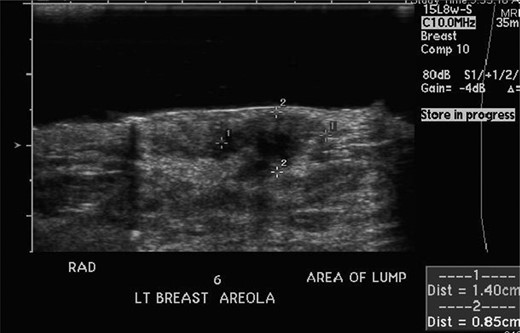

A 20-year-old female with a history of neurofibromatosis, and left breast supernumerary nipple excision presented to her primary care physician, after noticing a lump in her left breast at the site of her previous surgical scar after accidentally bumping her breast in January 2012. Her primary care physician then referred her to the breast surgery clinic at St. Barnabas Hospital. She was seen and examined at the breast clinic, where a palpable firm 1 × 1 cm mass was identified at the 6 O'clock position. She denied any nipple discharge. The decision was made to obtain an ultrasound (seen in Fig. 1) with close follow-up in the breast surgery clinic.

She returned to clinic later in January after the ultrasound, which revealed a 1.4 × 0.9 × 1.8 cm fluid collection at the 6 O'clock position most likely representing a hematoma; BIRADS #3 likely benign recommend short-term follow-up. She was scheduled for a repeat ultrasound in April 2012 with follow-up in breast clinic following the ultrasound. Repeat ultrasound (seen in Fig. 2) revealed a stable fluid collection measuring 1.5 × 1.2 × 2.2 cm, once again BIRADS #3 likely benign recommend short-term follow-up with the breast surgeon. She was seen in clinic following the ultrasound in April and reported decreasing pain and no nipple discharge, she was given a 1-month follow-up appointment.